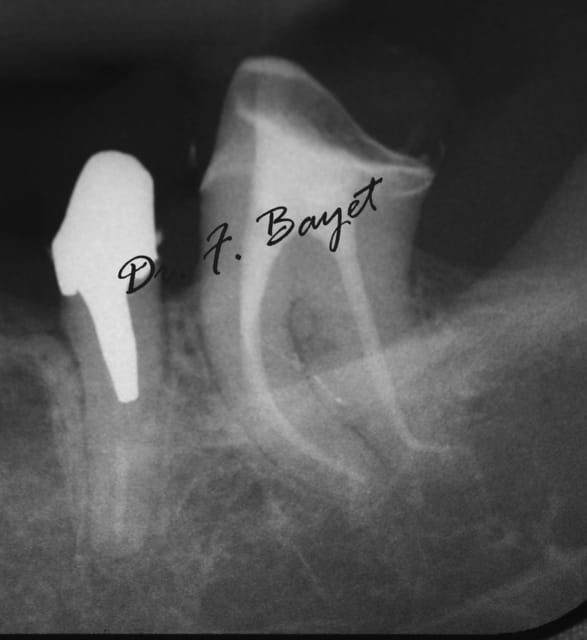

Ici avec de l'AlphaKite de chez Komet: lime 25 6% pour la 24 et Lime 25 6% puis finition 25 8% pour la 25.(moteur ATR sens de rotation horaire > antihoraire).

Img 0636 copie kylsbt - Eugenol